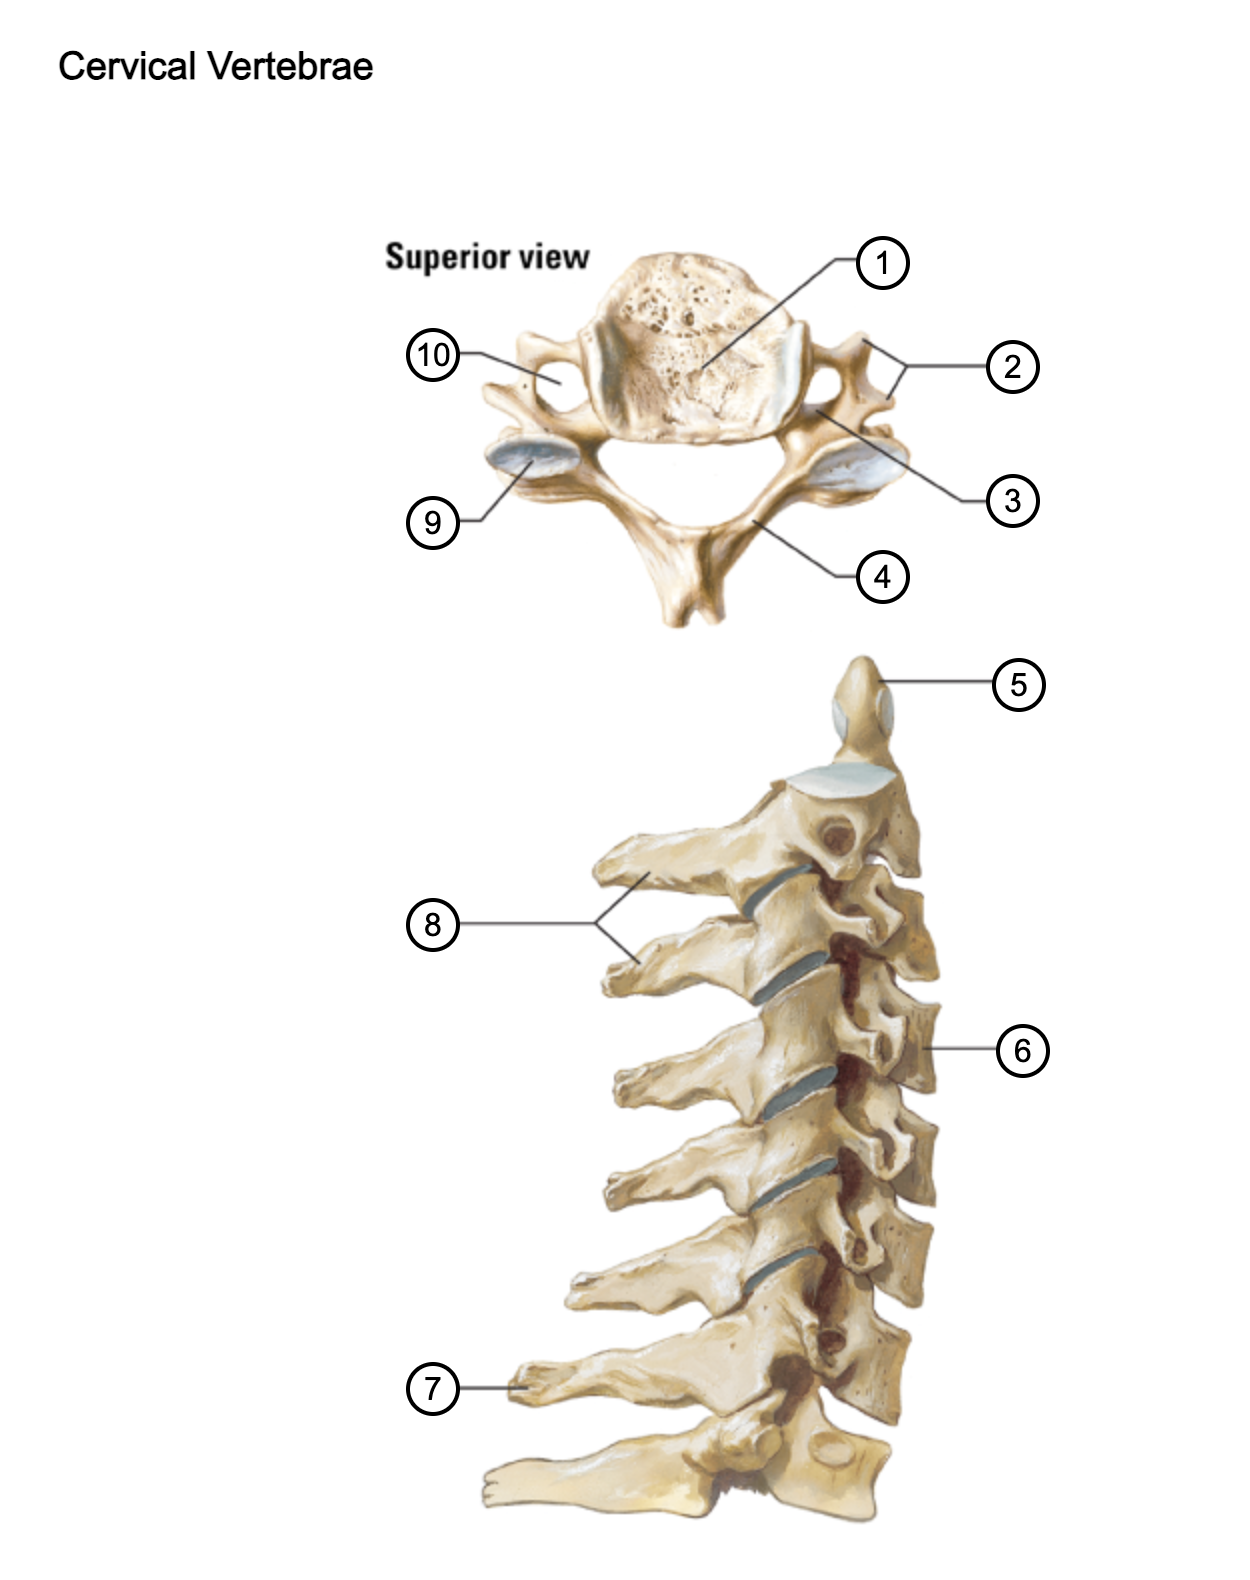

1

vertebral body

2

transverse process

3

pedicle

4

lamina

5

dens axis

6

vertebral body of C4

7

spinous process C7 (vertebra prominens)

8

spinous processes (C2 and C3)

9

superior articular process of C4

10

transverse foramen